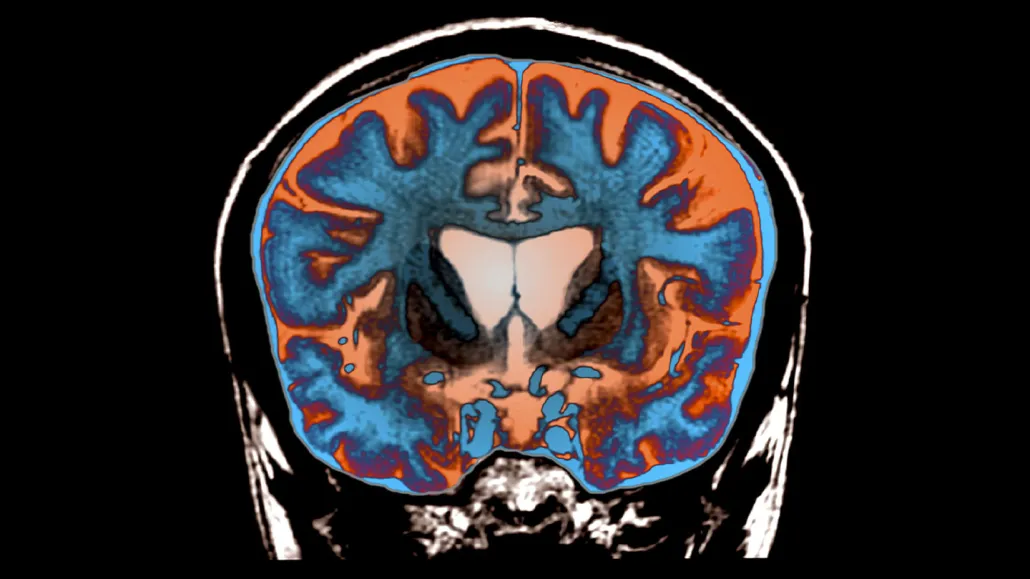

Huntington’s disease causes certain brain regions to die, as indicated by the darker areas in the center of this MRI image of the brain of a 21-year-old with the disease. Researchers have discovered that adding extra DNA to the gene that causes the disease leads to brain cell death.

Zephyr/Science Source